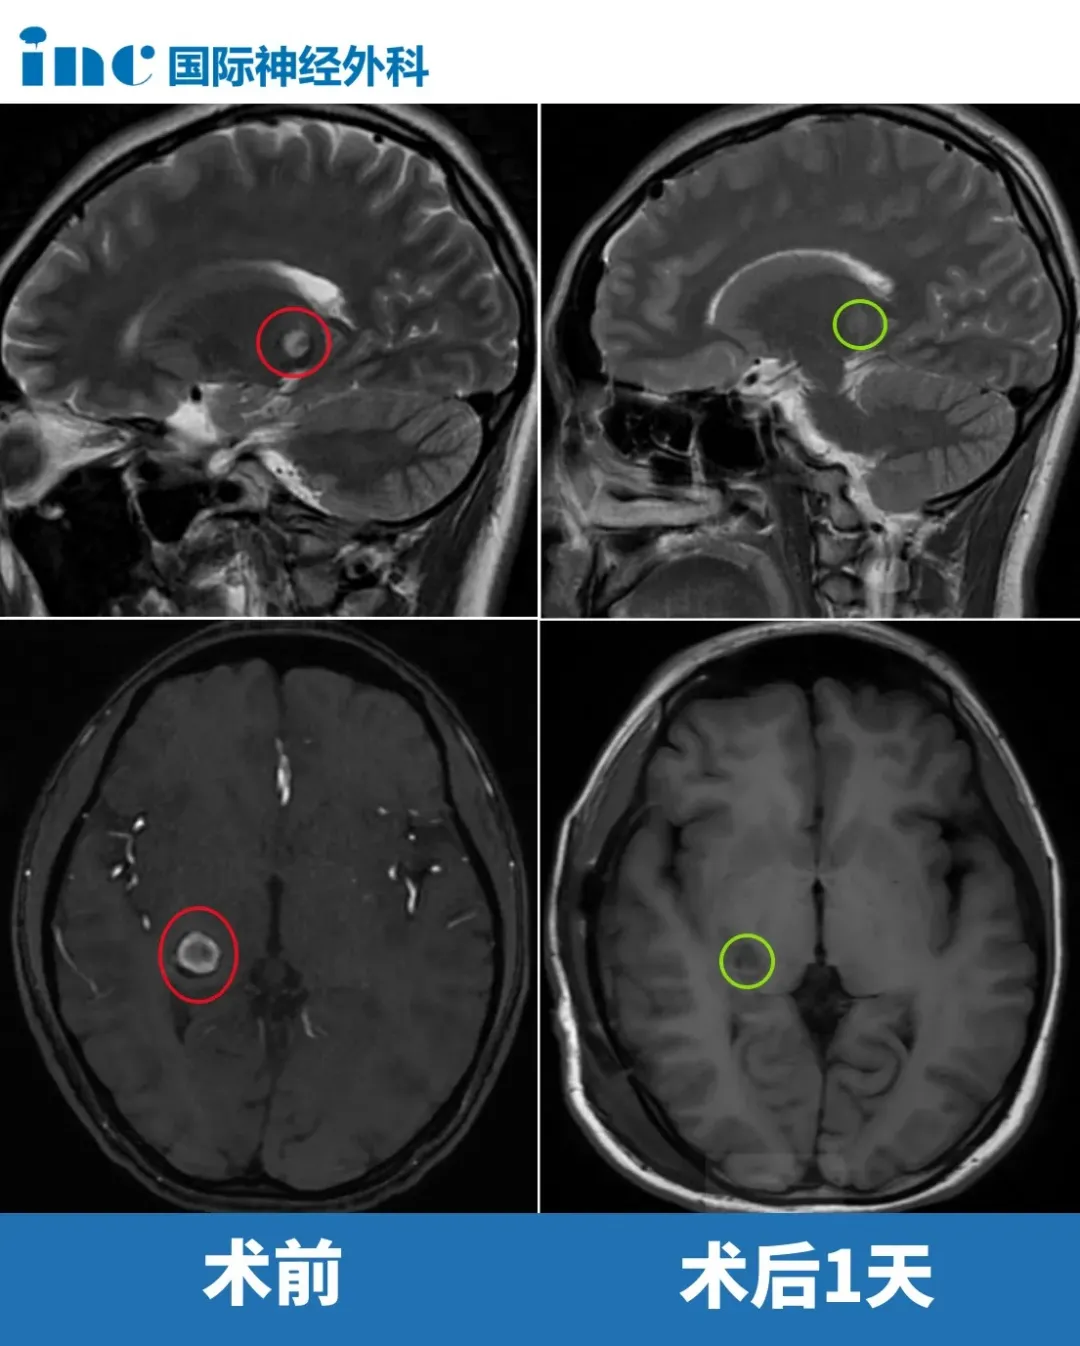

2024年6月7日,复合手术室的无影灯亮起。巴教授凭借着对大脑解剖结构的精准掌握,以及多年积累的疑难手术经验,在显微镜下小心翼翼地分离着脑组织,一点点靠近位于丘脑的病灶。最终为小雨顺利全切病灶。

术后第一天巴教授查房时,令人欣喜的一幕出现了:小雨在病床上自如地伸展着手脚,脸上重现了久违的笑容。

那个曾经被病痛折磨得失去活力的女孩,眼神里再次充满了青春的光彩。家人也一改往日的愁容,病房里终于有了欢声笑语。